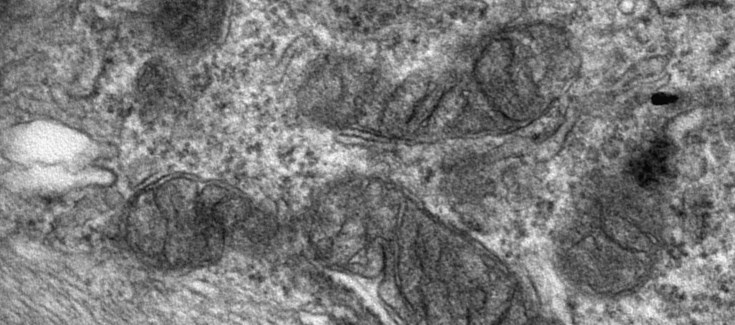

Micrografía electrónica de un astrocito hipertrófico en el nervio óptico de un ratón deficiente en Nr2f1. Foto: P. Bovolenta

El principal objetivo del estudio ha sido recrear en el laboratorio un modelo de esta enfermedad a fin de poder comprender los mecanismos celulares y moleculares que conducen a una disminución gradual de la agudeza visual en los niños afectados. El grupo francés y el que lidera la Dra. Bovolenta analizaron en detalle el desarrollo del nervio óptico en el ratón normal y tras la mutación en el gen NR2F1. El nervio óptico conecta la retina con el resto de las estructuras cerebrales importantes para la visión, por lo que es fundamental para un perfecto funcionamiento del sistema visual en el adulto. Ambos grupos demostraron degeneración o atrofia del nervio óptico en los ratones.